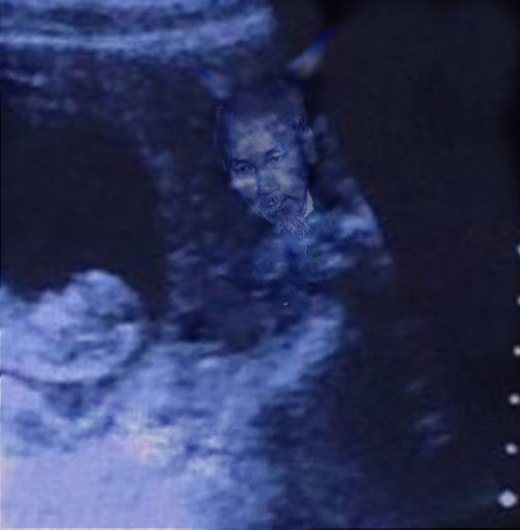

Mới đây, hình ảnh siêu âm thai của một người phụ nữ đã khiến cộng đồng mạng hoang mang tột độ. Cụ thể là trên bức ảnh đó bất ngờ xuất hiện hình ảnh giống như của “quỷ dữ” bên cạnh bào thai. Từ lúc bức ảnh được đăng tải trên mạng đã có rất nhiều luồng ý kiến trái chiều về hình ảnh của “quỷ” đó.

Cận cảnh hình ảnh siêu âm

Thông thường, khi siêu âm người ta chỉ nhìn thấy em bé. Tuy nhiên mới đây, hình ảnh “quỷ dữ” xuất hiện trên màn hình bên cạnh thai nhi làm cho mọi người không khỏi giật mình. Nếu nhìn lướt qua, có thể nhiều người nghĩ đây là một bức ảnh siêu âm bình thường như bao ảnh siêu âm khác.

Theo tờ báo nổi tiếng của Anh Express mô tả, hình ảnh siêu âm có thể bình thường khi mới nhìn vào với thai nhi trong bào thai. Nhưng nếu quan sát kĩ hơn, nhất là ở góc phải, ta sẽ thấy hình ảnh của một người khác với khuôn mặt dữ tợn đang nhìn vào thai nhi.

Bức hình siêu âm này sau đó được đăng tải lên Imgur với chú thích: “Hình ảnh siêu âm thai nhi của một người bạn. Bạn thấy gì khi nhìn vào?”.

Với nội dung rùng rợn này, bức ảnh lập tức được phát tán một cách chóng mặt. Liên tiếp các bình luận được đưa ra. “Tôi thấy một con quỷ bên phải”, tài khoản Blind bình luận. “Không, nữ thần Hindu mới đúng chứ!”, bạn Lizzie cho biết. “Ủa sao tôi không thấy con quỷ nào nhỉ? Một nàng tiên cá thân thiện mà!”, một người khác phản bác.